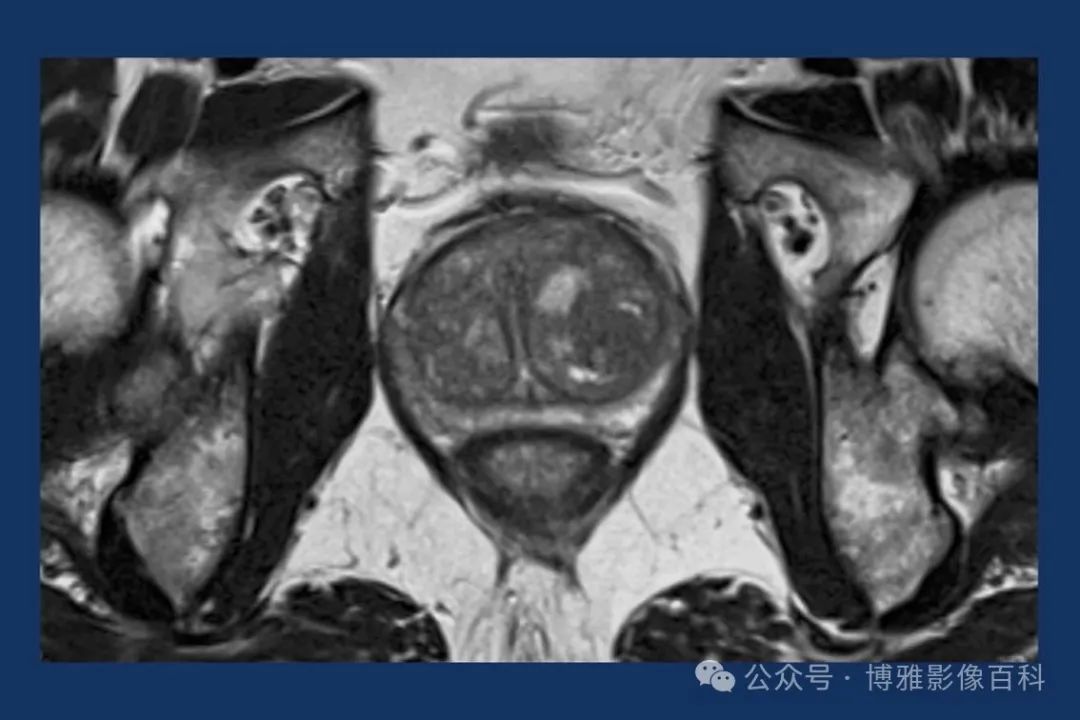

MR 解剖学

前列腺良性增生患者的轴向T2 图像,其他方面正常。外周带是一薄层均匀的高信号,边界清晰连续性的低信号包膜。移行带通常表现为不均匀中等信号,病灶被边界清楚的BPH良性前列腺增生结节所取代。精囊具有均匀T2高信号。未见淋巴结肿大。